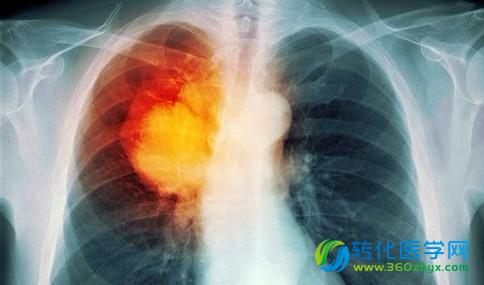

布洛芬可以降低吸烟者肺癌死亡的风险

布洛芬是一种常用于减轻疼痛和炎症的药物,但一项新的研究表明,其益处并不止于此。研究人员发现,该药物还可以降低吸烟者肺癌死亡的风险。

肺癌是美国最常见的癌症之一,约占新发癌症病例的14%。

今年,估计美国约224,390人将被诊断患有肺癌,超过158,000美国人将死于该疾病,肺癌成为男性和女性癌症死亡的主要疾病。

吸烟是肺癌的主要原因,美国约80-90%的肺癌病例与此有关。

根据疾病控制和预防中心(CDC),吸烟者比不吸烟者发生肺癌或死于该疾病的可能性高15-30倍。

以前的研究表明,慢性炎症与肺癌的风险增加有关。由于布洛芬是一种消炎类药物,Bittoni博士和同事开始调查该药物是否有益于有吸烟史的人。

布洛芬将肺癌死亡风险降低了48%

总体而言,研究小组发现,常规使用布洛芬的前或目前是吸烟者的比未使用该药的患者肺癌死亡率降低48%。

作者报告说,肺癌死亡风险与使用阿司匹林(另一种常见的NSAID)之间的联系不具有统计学意义。

戒烟和采取健康的生活方式仍然是降低肺癌风险的最好方法。然而,Bittoni博士和同事相信他们的研究结果表明布洛芬的常规使用可能对一些人有价值。

“这些结果表明,定期使用某些NSAID药物可能有利于预防吸烟者患肺癌,并作为肺癌预防策略。”